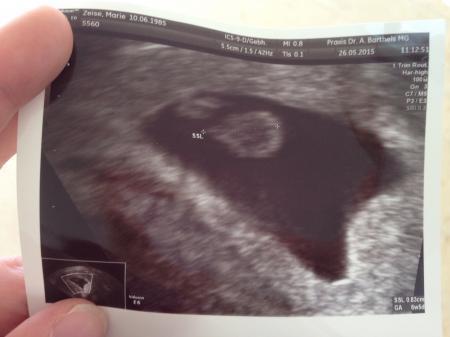

Hallo, War heute morgen beim FA. Bin heute ca 6+5. der Krümel hat die exakte Größe für 6+5, aber leider ist kein Herzschlag zu sehen :( Muss in einer Woche nochmal hin. Mach 16 Monate Wartezeit hatte es endlich geklappt und nun das?! Meint ihr es besteht noch Hoffnung :( Bin dieses Mal extra später zum FA gegangen, aber gebracht hat es mir nichts :( Bin so traurig, alles erinnert an die FG von 2010 :( Anbei mal ein Foto von dem Häufchen.... Liebe Grüße